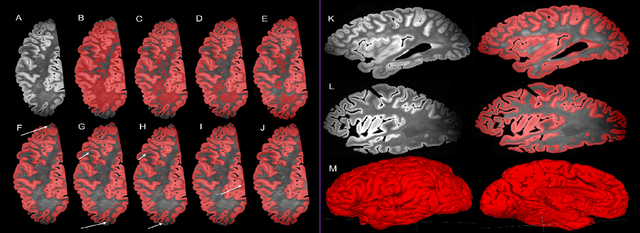

Ex vivo MRI of the brain provides remarkable advantages over in vivo MRI for visualizing and characterizing detailed neuroanatomy. However, automated cortical segmentation methods in ex vivo MRI are not well developed, primarily due to limited availability of labeled datasets, and heterogeneity in scanner hardware and acquisition protocols. In this work, we present a high resolution 7 Tesla dataset of 32 ex vivo human brain specimens. We benchmark the cortical mantle segmentation performance of nine neural network architectures, trained and evaluated using manually-segmented 3D patches sampled from specific cortical regions, and show excellent generalizing capabilities across whole brain hemispheres in different specimens, and also on unseen images acquired at different magnetic field strength and imaging sequences. Finally, we provide cortical thickness measurements across key regions in 3D ex vivo human brain images. Our code and processed datasets are publicly available at https://github.com/Pulkit-Khandelwal/picsl-ex-vivo-segmentation.